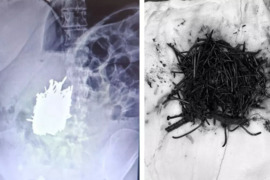

Qadının mədəsindən 1 kilo metal əşya tapıldı

Mersinin Erdemli rayonunda əqli qüsurlu qadın xəstənin mədəsindən 1 kiloluq metal əşya tapılıb. xarici mediaya istinadən xəbər verir ki, rayonda yaşayan əqli qüsurlu A.K. qarın ağrısı şikayəti ilə Erdemli Dövlət Xəstəxanasına müraciət edib. Xəstə üzərində aparılan müayinə nəticəsində qadının mədəsind